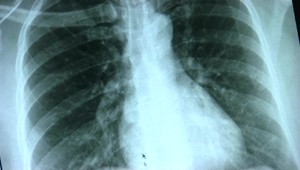

Zápal pľúc rozhodne nie je banálne ochorenia môže ohroziť život. Je infekčné a dostať ho môže každý z nás. Príznaky, najmä u starších ľudí bývajú dosť netypické a nie je vždy je prítomná horúčka. Bohužiaľ, až 80 percent ľudí nad 80 rokov zápalu pľúc podľahne. Prečo je dôležité dať sa zaočkovať proti chrípke a pneumokokom a ako nosenie rúšok pomáhalo nielen proti kovidu? Vypočujte si rozhovor s pneumológom Štefanom Laššanom z Kliniky ftizeológie a pneumológie UN v Bratislave,